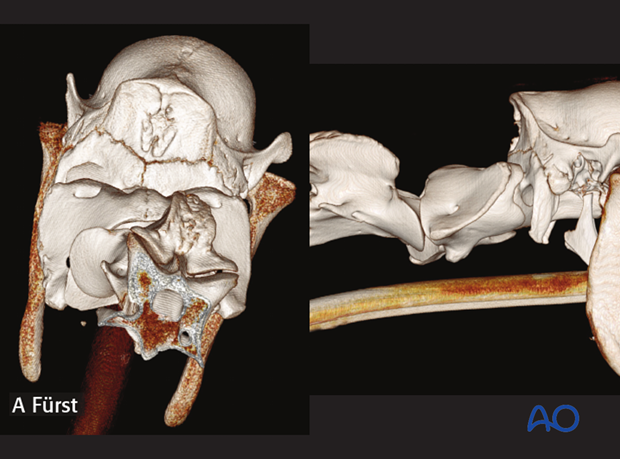

CT study showing the rotational (left) and dorsoventral (right) malalignment between C1 and C2.

2-year-old patient with a subluxation in C1-C2.